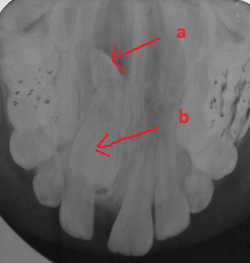

Răng thừa (b) mọc trong vòm miệng khiến cho R22 (a) mọc lệch xoay trục XQ răng toàn cảnh không thấy răng thừa do R21 (a) che khuất,(b) là R22 bị xoay trục

Hình ảnh răng thừa (a) xuất hiện rất rõ trên CT Cone Beam, (b) là hình ảnh R21

Hình 3: Tính ưu việt của CT Cone Beam trong chẩn đoán răng thừa

(Nguồn: Bệnh viện Đa khoa Tỉnh Quảng Trị)